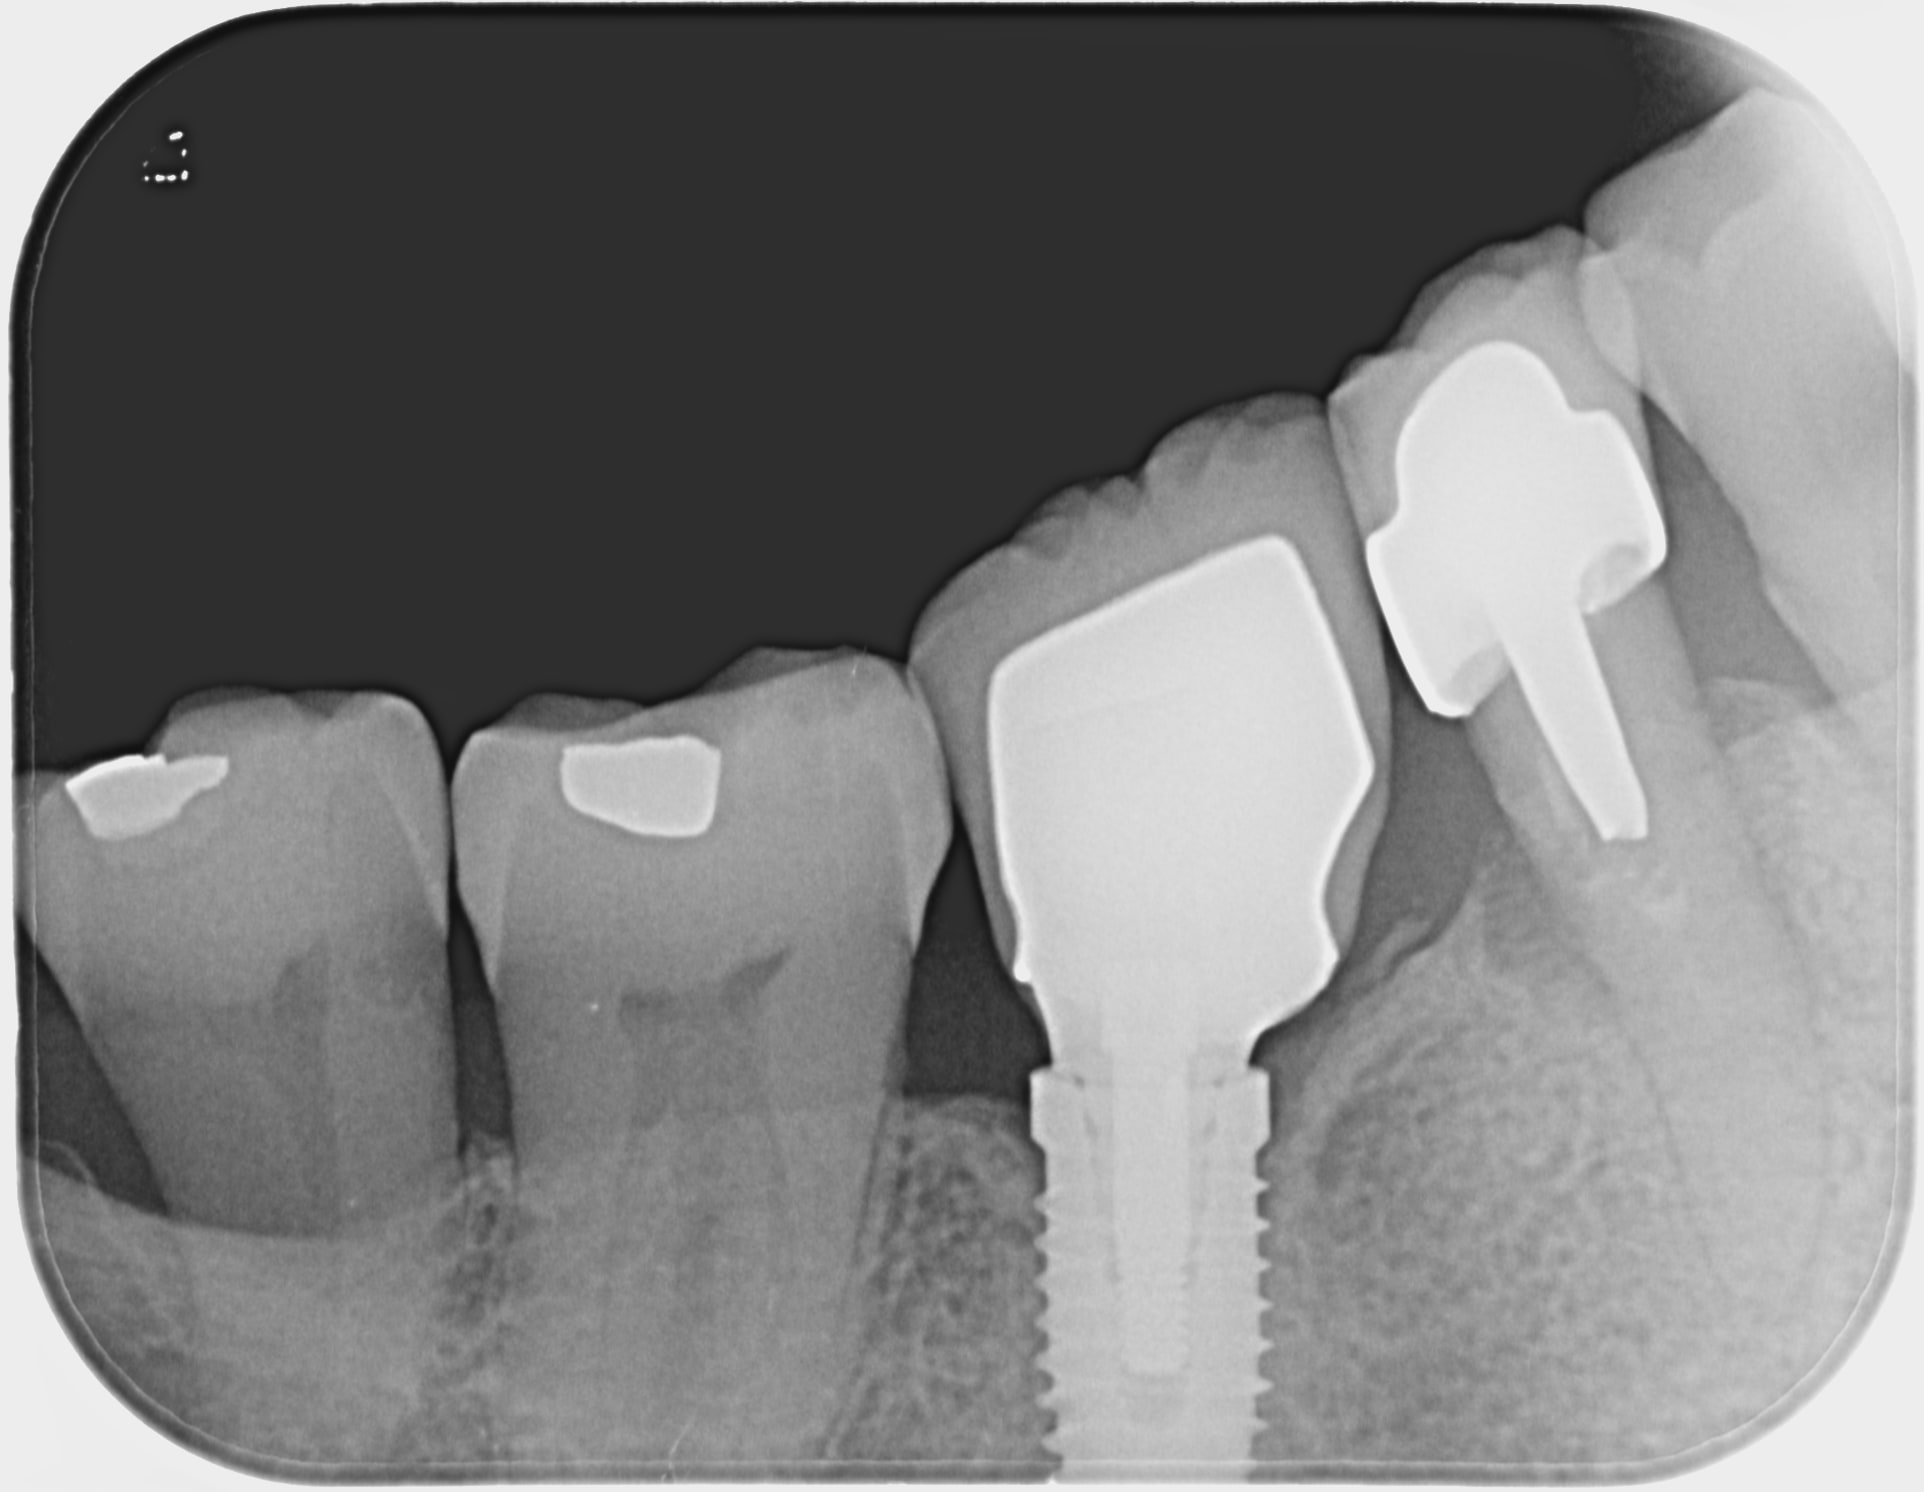

je cherche à savoir quel est cet implant dont la couronne est dévissée.